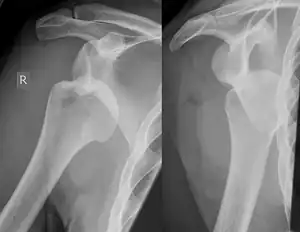

| Hill–Sachs fracture | Harold Arthur Hill Maurice David Sachs |

impacted posterior humeral head fracture occurring during anterior shoulder dislocation | Hill Sachs Lesion Archived 2020-09-20 at the Wayback Machine at Wheeless' Textbook of Orthopaedics online |

| |